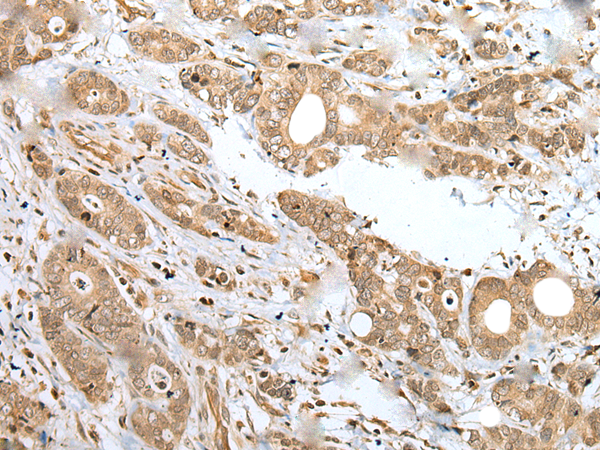

IHC positive control: |

Human gastric cancer |

IHC Recommend dilution: |

25-100 |